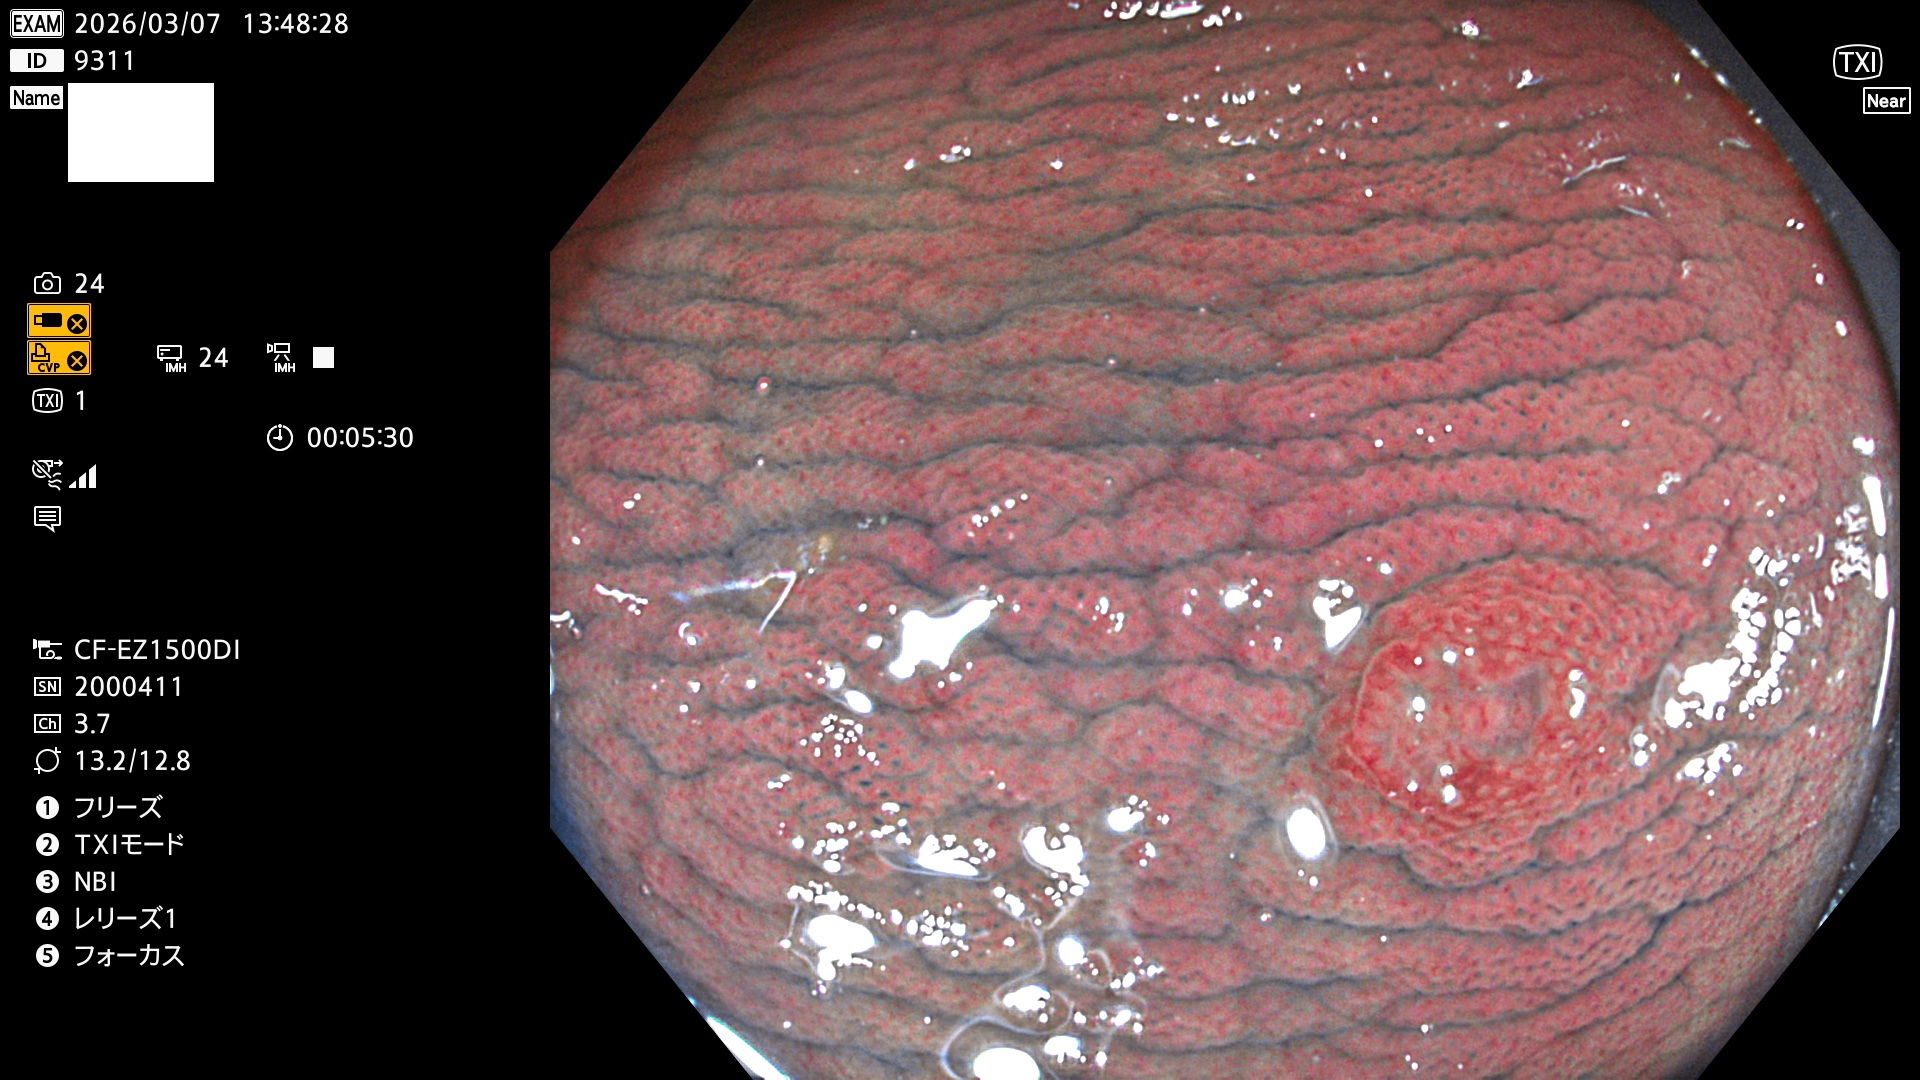

完全に平坦な物をUb、陥凹している物をUcと呼びます。Ubは認識が困難で、Ucはびらん(炎症)と紛らわしいために見落とされやすく、「内視鏡後・大腸癌」の原因になります。

専門的)Uc=De Novo癌? 内視鏡の解像度が低かった時代、このような説もありました。しかし今日の高精度内視鏡では良性の微小なUc型腺腫(APC遺伝子異常の腺腫)が日常的に見つかります。Ucこそが多段階発癌(Adenoma-Carcinoma Sequence)のMain Routeです。

毎週の検査(木・金・土・日)に発見されたUbとUc型・腺腫を、その週の日曜の夜にUPし1週間、提示します。

2026年3月5日〜3月8日の4日間(40件)9個 (Uc_ADR=9個/40人=23%)